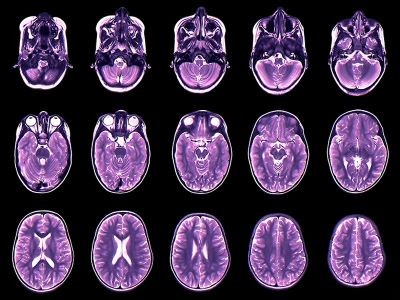

Scientists have created the first atlas of specific key patterns of brain ‘chatter’ and determined how these patterns change over the entire human lifespan1.

The comprehensive guide draws on brain scans from almost 3,600 people, ranging from infants to centenarians. It maps a property called functional connectivity, which describes the level of coordination between separate brain regions. The data suggest that in young adults, particular patterns of this connectivity are linked to cognitive performance.

To fill this gap, Taylor, Yap and their colleagues analysed functional magnetic resonance imaging (fMRI) scans — which reveal brain activity — of 3,556 people between the ages of 16 days and 100 years old. The researchers tracked how the three main functional scales developed and changed at different ages.